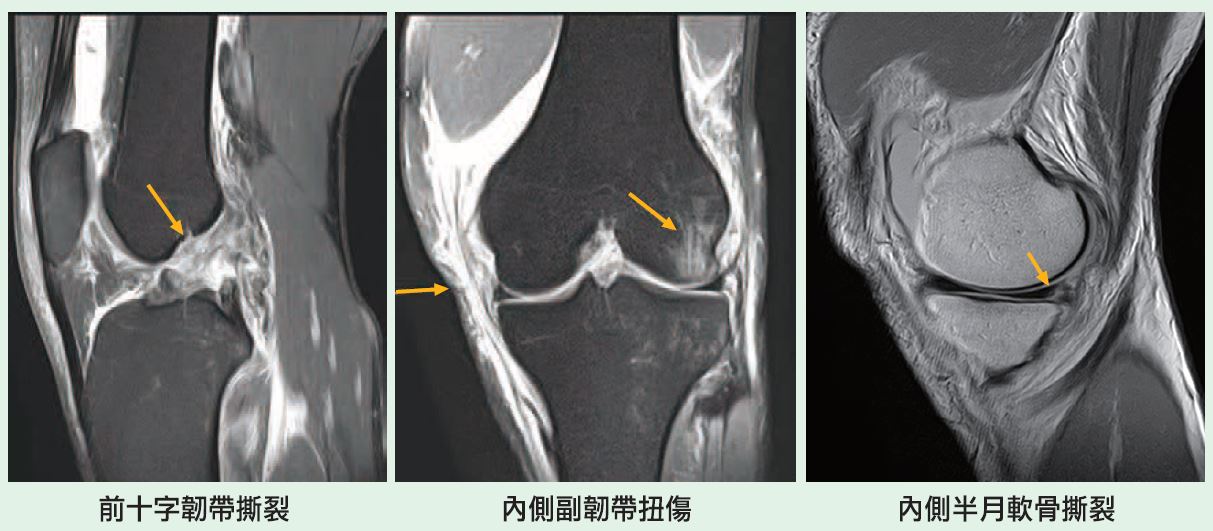

🔺常見的急性外傷性疼痛:病因包括內和外側韌帶撕裂、前十字韌帶撕裂、半月軟骨撕裂、膝蓋骨脫臼或半脫位、髕骨(膝蓋骨)韌帶撕裂、關節內骨折及骨軟骨缺損。

【案例一】

41歲男性工程師,近期因運動時摔倒受傷,左膝疼痛且無法上下樓梯。經磁振造影檢查,顯示前十字韌帶完全撕裂,內側半月軟骨撕裂及內側副韌帶扭傷,並出現大量關節積水及骨髓水腫。後續須進行韌帶修復及內視鏡手術治療。